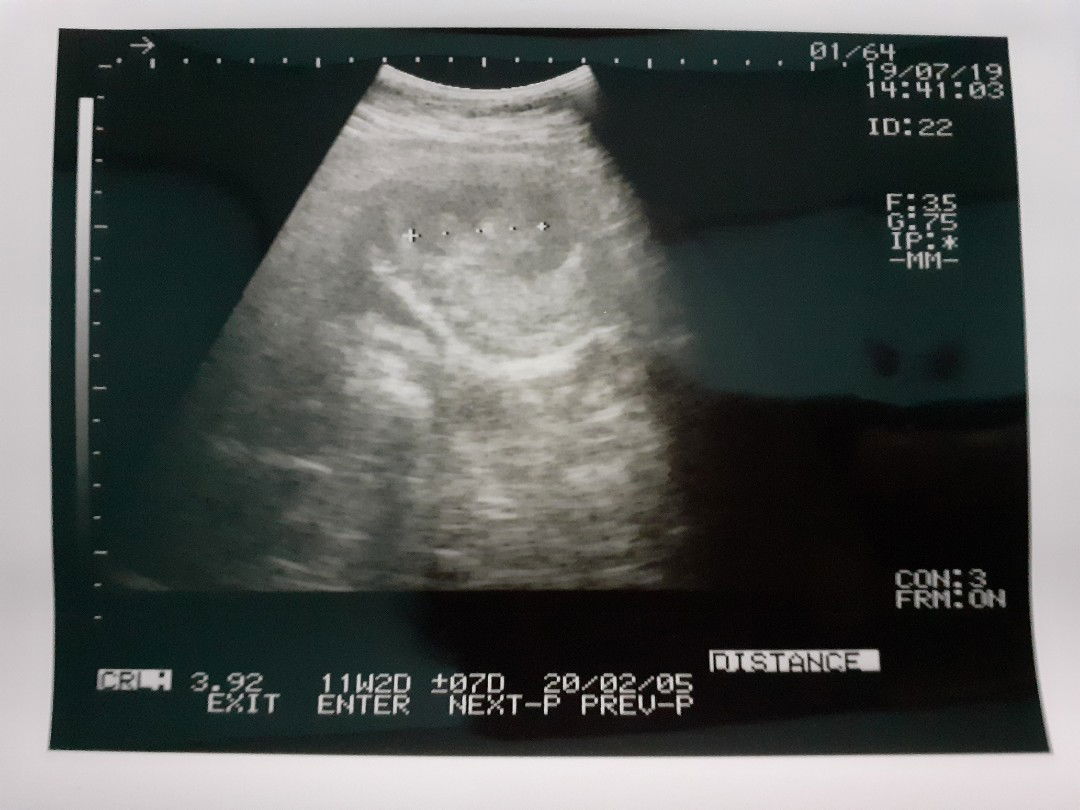

USG

Bun mau sharing, ini usg saya hari jumat 19 juli kemarin, kalau usia dr bisan 12 minggu lebih 2 hari tapi pas usg 11 minggu lebih sekian hari. Trs kata dokter janin saya ukurannya kurang, saya sudah berusaha makan dan minum walaupun mual mutah tetep saya paksa. Sudah minum susu bum walaupun 1 hari 1x lalu minum asam folat dan vitamin. Kata dokter suruh makan yg banyak aja. Tapi saya takut bun kalau janin saya knp2 ?. Menurut bunda apa yg harus saya lakukan, karena ini anak pertama bun, masih kurang pengalaman ?

Bunda, kok usia kehamilan dr bidan sama USG beda ya? Yg bener yg mana kira2?